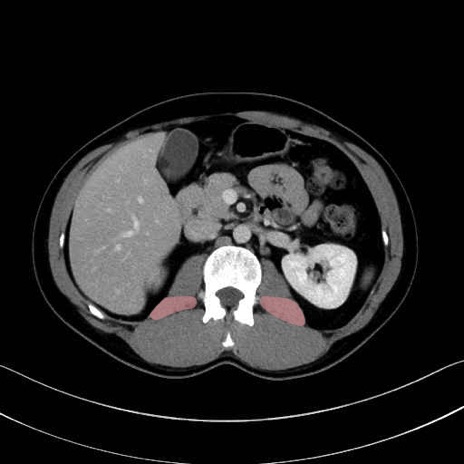

腰方形筋(quadratus lumborum muscle)のCT画像の解剖

1. 体幹部(腹部・背部・後腹壁)の筋肉

腰方形筋 (Quadratus lumborum)

脊柱起立筋 (Erector spinae)

多裂筋 (Multifidus)

大腰筋 (Psoas major)